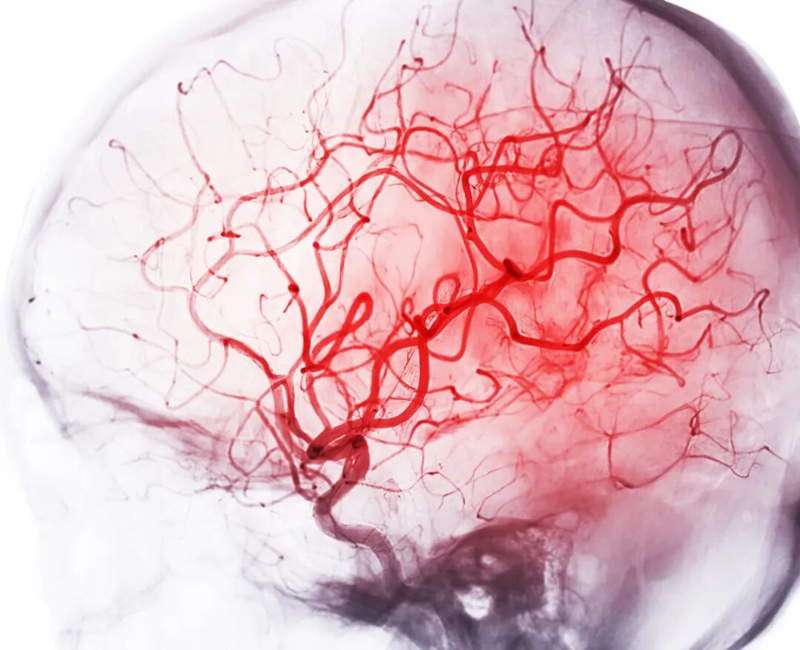

曾经被认为是“老年病”的脑出血,如今正将魔爪伸向风华正茂的年轻人。而悲剧的源头,大多指向同一个被忽视的警告——高血压。

持续的“内耗”:在你看不见的身体内部,高压血流正日复一日地冲击、磨损着你的血管内皮。就像一根常年超负荷承压的水管,管壁会变脆、受损,出现“小沙眼”样的微损伤。这些损伤处极易吸引血脂、胆固醇等物质沉积,形成动脉粥样硬化斑块,让血管变得更窄、更脆。

瞬间崩盘 当高血压引爆脑出血

脑出血,俗称“脑溢血”,是高血压最严重、最致命的并发症之一。高压的血液瞬间涌出,像洪水一样挤压、摧毁着娇嫩的脑组织。这就是脑出血。它来势凶猛,致死率、致残率极高。幸存者往往面临偏瘫、失语、认知障碍等严重后果,个人生活无法自理,整个家庭也随之坠入深渊。